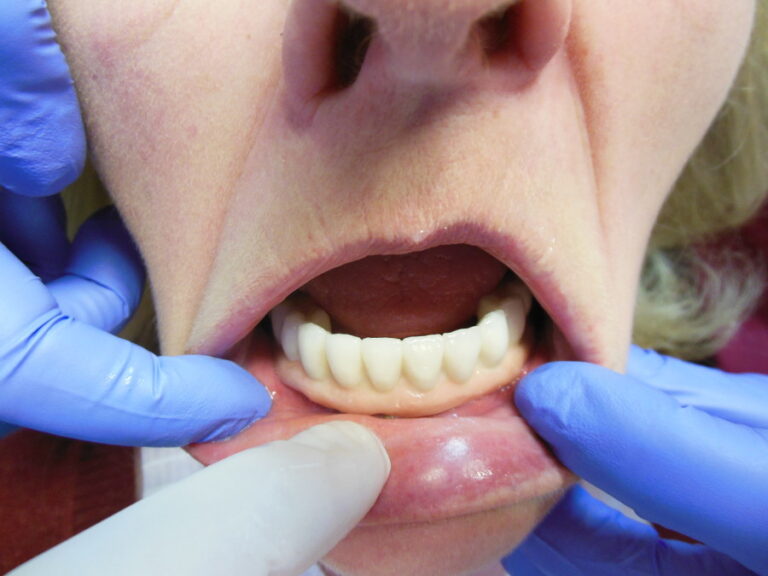

Implanty zygomatyczne

Przykłady implantologii

Zastosowanie implantoprotetyki w przypadku gdy klasyczna protetyka nie sprawdza się.